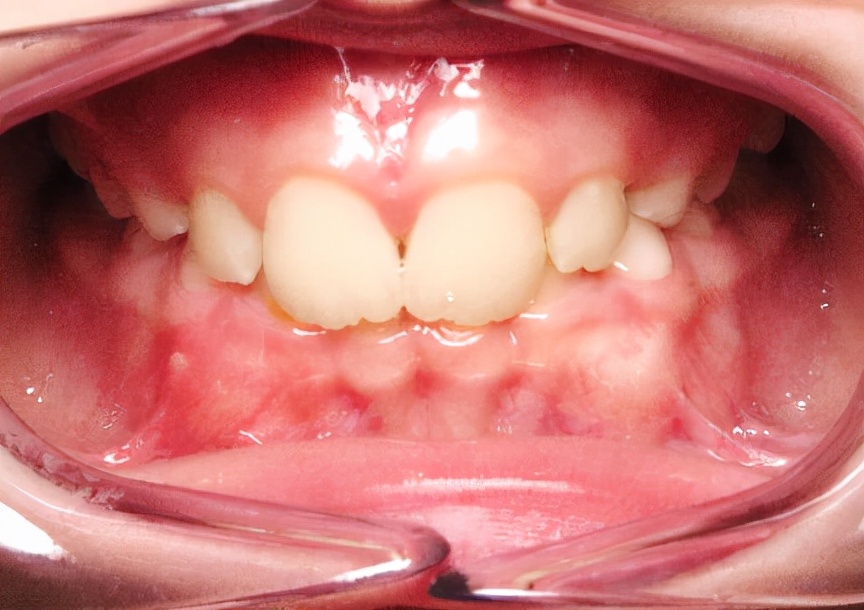

1.替牙列期前牙深覆合

(图为闭锁性深覆合矫治前后对比)